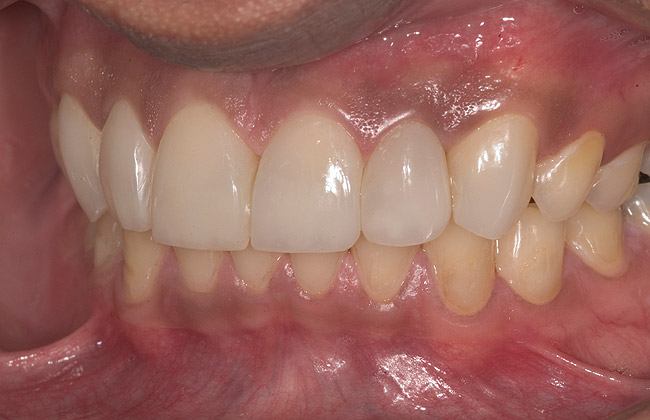

White enamel shade was placed on the putty index and carried to the palatal surface of No. 9. This layer was spread uniformly and thinned out and spread along the entire width of the tooth (Figure 11). After curing this layer, A2 dentin was layered to simulate the lobular pattern seen in dentin of the natural teeth (Figure 12). After curing, a layer of transparent resin was placed in the incisal areas between the dentinal lobes. The final layer of A2 enamel was built and shaped to full contour (Figure 13). A similar build-up was done for all the remaining anterior teeth. The bite in MIP was adjusted such that there was uniform contact on all anterior teeth. The anterior guidance was harmonized to maintain uniformity in the contact of the incisors during protrusion and the canines and incisors during lateral excursions. Finishing and polishing was done per protocol (Figure 14 through Figure 18).13

Figure 14  Postoperative smile.

Figure 14

Figure 15  Maximum intercuspation (MIP) after restoration of the lost palatal anatomy.

Figure 15

Figure 16  1:2 right lateral view; posteriors discluded in MIP.

Figure 16

Figure 17  1:2 left lateral view; posteriors discluded in MIP.

Figure 17